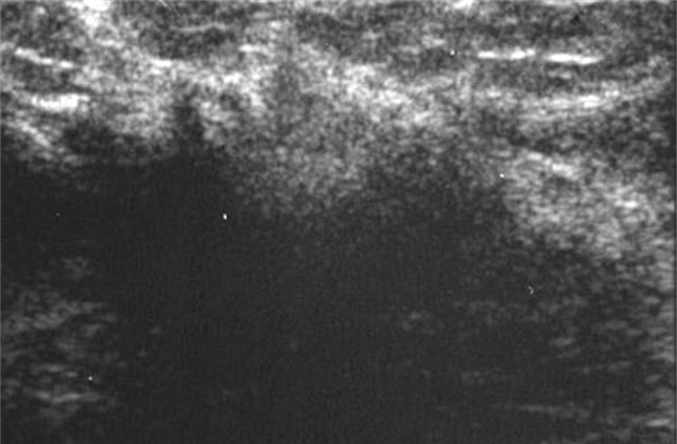

What are these images showing?

invasive lobular carcinoma